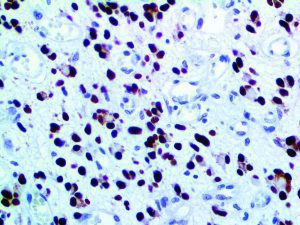

It is the ICU physician who is most likely to witness one of the deadliest manifestations of the abnormal immunological response, the cytokine storm syndrome (CSS). This response is also referred to by some as the cytokine release syndrome (CRS). CSS is characterized by continuous activation and expansion of macrophage and lymphocyte populations, which secrete large amounts of cytokines, causing the cytokine storm. This massive cytokine release is akin to hemophagocytic lymphohistiocytosis (HLH) disease, a syndrome characterized by initial unchecked and persistent activation of cytotoxic T lymphocytes and NK cells.

Clinical and laboratory manifestations of HLH include fever, enlarged liver and/or spleen, neurologic dysfunction, coagulopathy, liver dysfunction, cytopenias (i.e., low levels of erythrocytes, leukocytes, and/or platelets), hypertriglyceridemia, hyperferritinemia, hemophagocytosis, and eventually diminished NK cell activity as the immune system becomes progressively paralyzed. HLH can be familial (primary HLH) or secondary to another disease process (sHLH), such as rheumatic disease, in which it is referred to as macrophage activation syndrome (MAS, characterized by elevated ferritin).